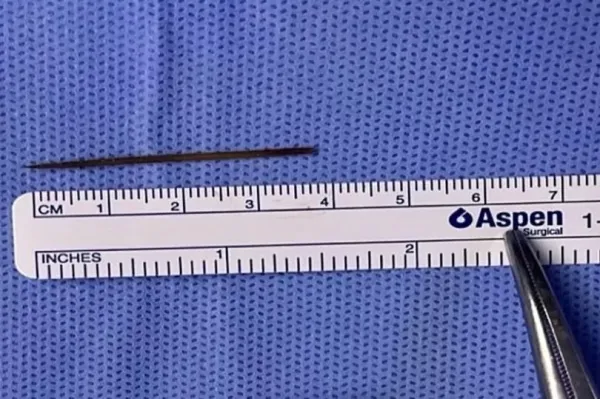

Doctors were baffled until they sent him for a CT scan which unearthed a small “structure” measuring 3.7cm. They assumed it was an accidentally-ingested bone from his dinner.

The medics then ordered an emergency laparoscopy to investigate further, and that's when they found the cause: a wooden toothpick, which had perforated the bowel, as reported by NeedToKnow.

Doctors then went to share their findings with the patient, at which point he “recalled sleeping with a toothpick in his mouth” the day prior to the start of his symptoms, for unknown reasons.